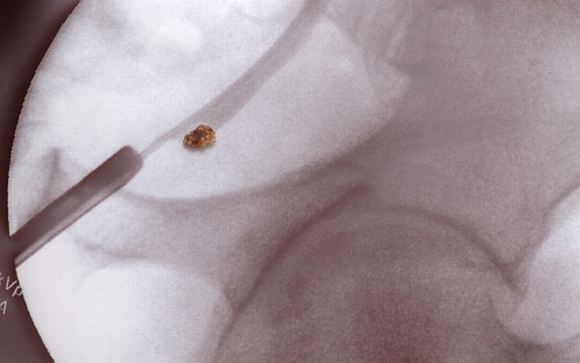

A vesekövek ásványi sóból képződött kicsi és kemény lerakódások a vese belsejében. Amikor a vizelet túl koncentrált, az már egy jele lehet a későbbi vesekőképződésnek. Először kristályok képződnek, amelyek idővel nagyobb kővé érnek össze.

Elegendő folyadék fogyasztásával azonban sokat lehet tenni a megelőzésért. Eltávolításának módja a kő méretétől függ. Ha kisebb, akkor jó eséllyel spontán módon eltávolodik. Sok víz fogyasztása és fájdalomcsillapító szerek szedése segíthet ebben. Nagyobb kövek esetén azonban invazív beavatkozásokra lehet szükség. A műtét során a húgycsövön keresztül vezetnek fel egy csövet, amely szétzúzza a nagyobb köveket kisebb darabokra, amelyek könnyebben eltávolodnak a szervezetből.